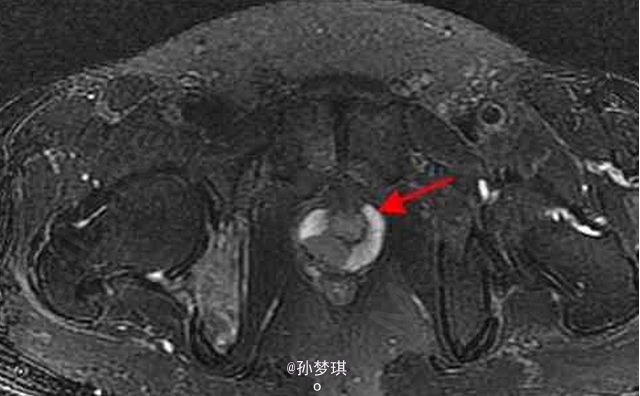

男,70岁,因排尿困难7年,加重3月前来就诊

患者除排尿困难外无其他不适症状 辅查MRI,T2W示前列腺外周带正常高信号环中断,信号不均匀升高;增强T1WI示前列腺外周带偏右侧增厚,右侧坐骨支不均匀强化